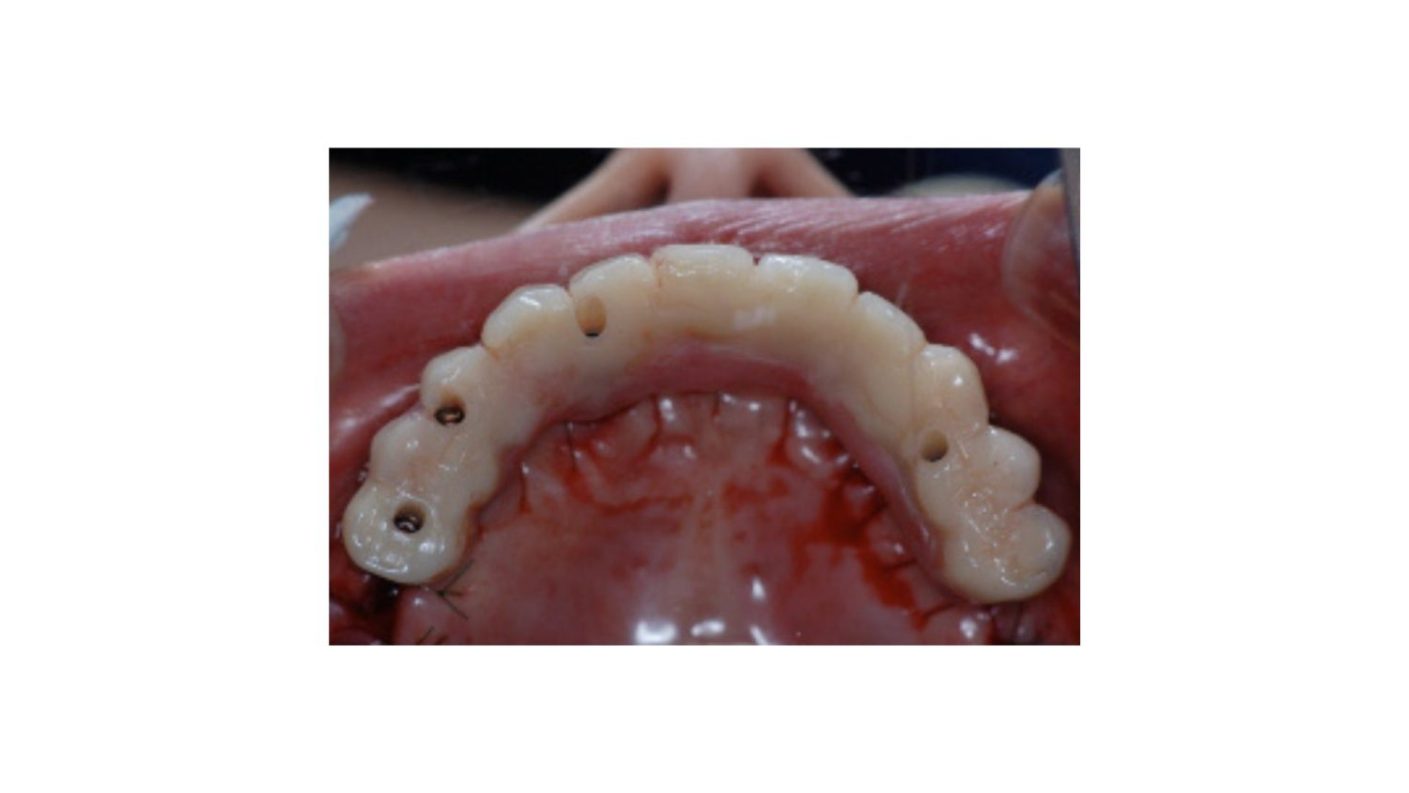

| 主訴 | 全顎治療希望、歯が無いので噛みずらい。定年で時間の余裕出来たので、インプラントで治療して欲しい。 |

| 治療内容 | プラークコントロール不良なため歯周治療を行い、残存歯を極力温存し、欠損部インプラントを施し咬合再構成を行う。 プロビジョナルレストレーションによる咬合関係を模索した後、全顎にわたりセラミックによる補綴治療、その後メインテナンスに移行 |

| 治療費 | 6,470,000円(税込)(インプラントすべて含む) |

| 治療期間 | 1年6ヶ月 |

| 治療回数 | 72回 |

| 想定されたリスク | 食いしばり(パラファンクション)によるセラミックの破折、歯の破折 |